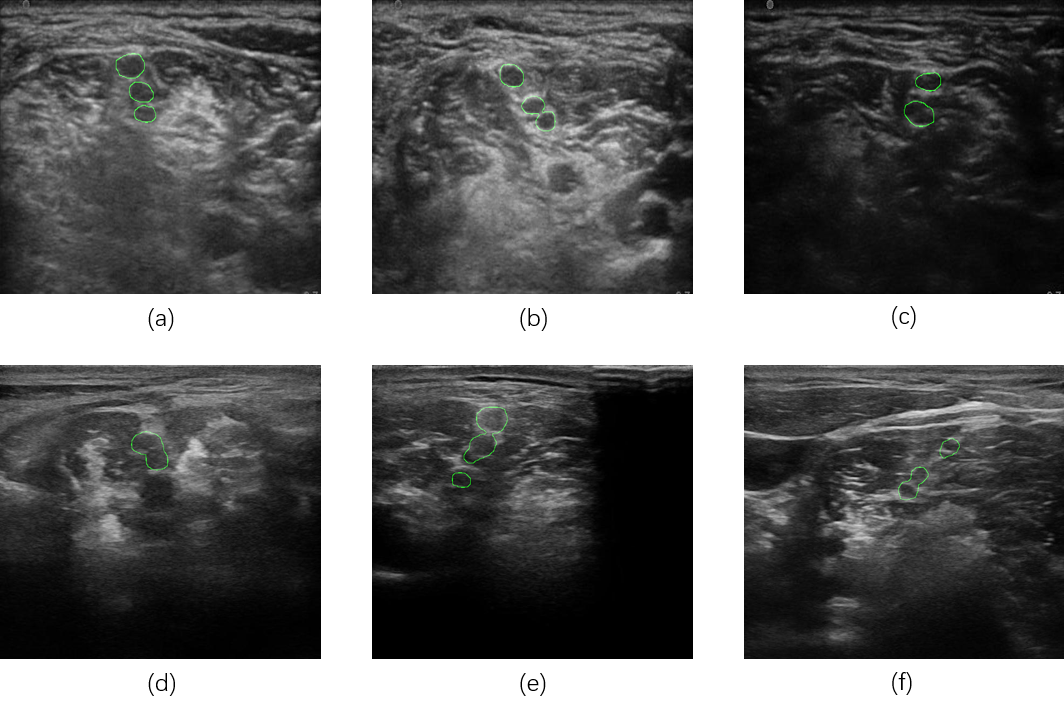

With this study, we built BPSegData to develop an AI BPSegSys. BPSegData is collected using two ultrasound devices, 185 BPUS (YGY dataset) collected using YGY equipment and 135 BPUS (BK3000 dataset) collected using BK3000 equipment, a total of 320 images. Three experienced doctors labeled the 320 images for BPSegData to ensure the accuracy of the brachial plexus trunks segmentation label. Using this dataset, we developed an AI system for the precise segmentation of the brachial plexus trunks, assisting the anesthesiologists to accurately identify the brachial plexus trunks for anesthesia. The developed BPSegSys can form an automated brachial plexus trunk segmentation pipeline, which consists of two modules: (1) BPUS preprocessing module, (2) brachial plexus trunks segmentation module. We cropped, enhanced, and augumented the original ultrasound images in the preprocessing module and used deep learning methods to segment the brachial plexus trunks in the segmentation module. In order to accurately evaluate the performance of BPSegSys and the reliability of the verification model, we used the 10-fold cross-validation method. Some final segmentation results of BPSegSys are shown in Figure 1.

Refer to caption

Fig. 1: The final segmentation results of BPSegSys. (a), (b), and (c) are from YGY dataset images. (d), (e), and (f) are from BK3000 dataset images.